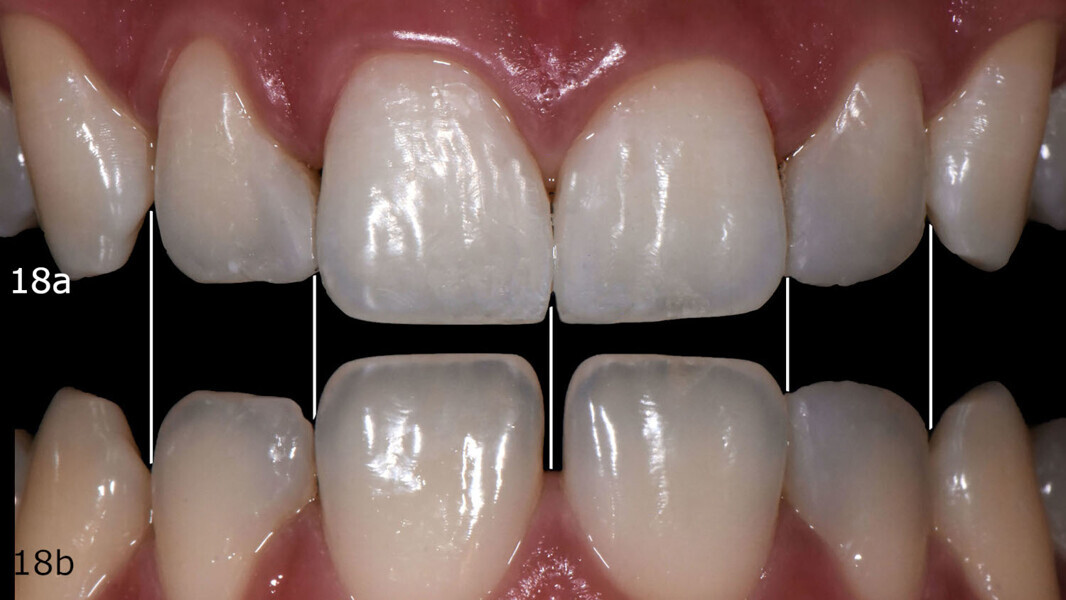

At the six-month follow-up appointment, the patient’s situation was very different to that at the initial consultation. There was proper closure of the interdental gaps and consequent formation of papillary tissue that harmonised the shape of the attached gingiva and of the reconstructed enamel perimeter (Figs. 18–21). In addition, the examination showed no fractures of the restoration or wear, no marginal discoloration or other staining, adequate marginal seal, adequate colour stability and translucency, very good surface structure and anatomical shape, excellent contact points, very good integrity of the teeth and no inflammation.

Figs. 18a & b: Space closure comparative check on the digital smile design before (a) and after (b).